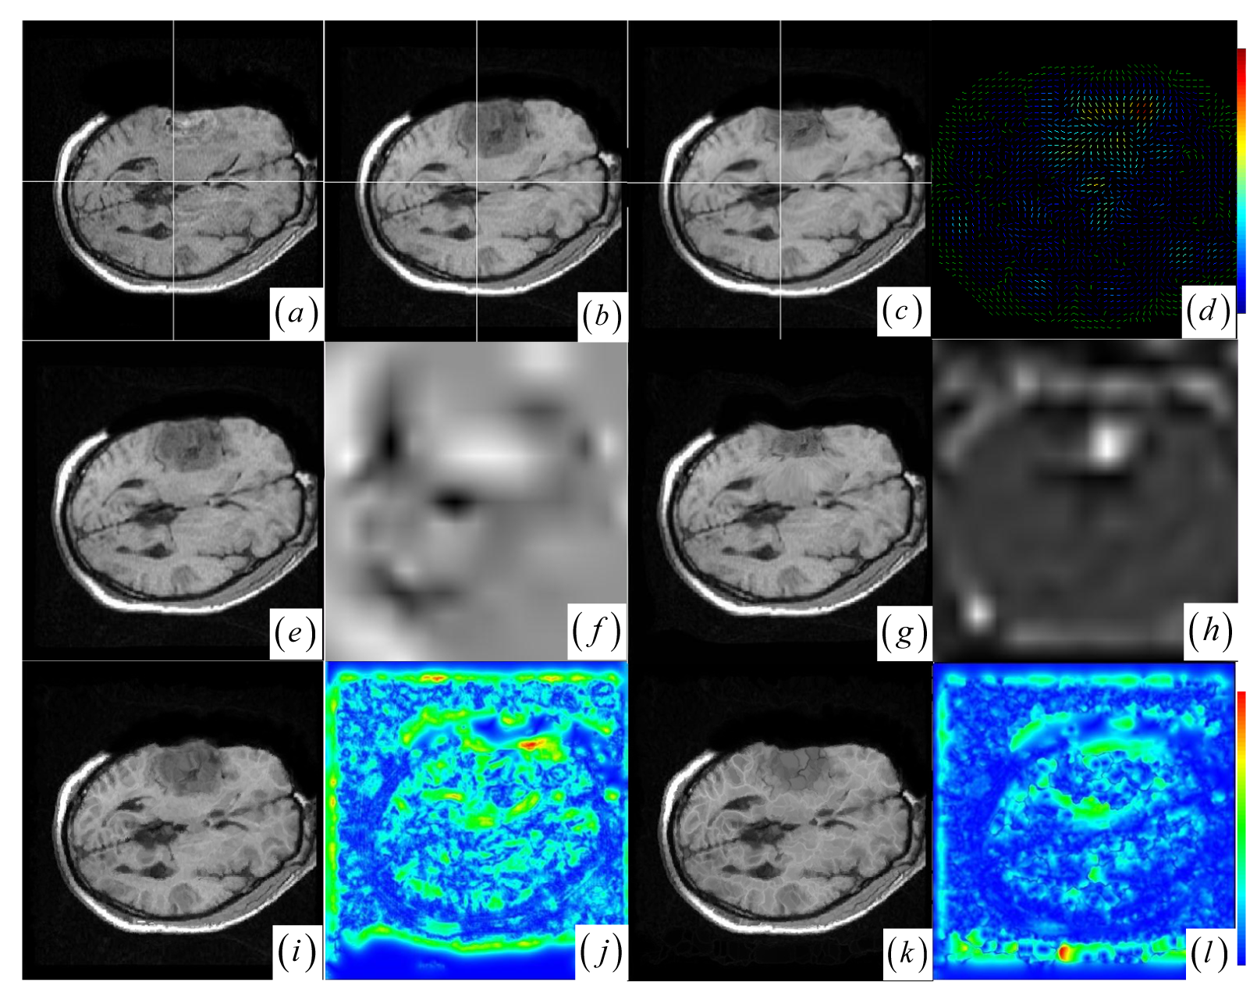

A JSM value near one suggests that the underlying pixel pair comes from the corresponding spatial structures. Contrarily, a JSM value near zero indicates that the pixel pair originates from either the outliers or a homogeneous region. To speed up the rigid registration procedure without reducing accuracy, the registration only uses the salient pixel pairs with large saliency values. The pixel with a small saliency value below a fixed threshold value (10 percent of the maximum saliency value) is assigned zero JSM value directly. Generally, the JSM would primarily respond to the high-gradient common edges in both images if a high threshold is chosen to exclude more pixels from estimating the JSM. However, as in the Figure 1c–e representing the image gradient and the JSM profiles of the same line at the two registered images (see Figure 1a,b), the JSM (see Figure 1e) consistently captures the corresponding regional salient structures in the two images while the image gradient features (see Figure 1c,d) are very noisy and do not agree with each other at each overlapping location.

The accurate rigid registration can be iteratively achieved by maximizing the MI between the corresponding salient structures that are highlighted by the JSM. The JSM is updated with the transformation T changing the overlapping area of the two images during the rigid registration. Specifically, the JSM weights each overlapping pixel pairs for the joint histogram so that the contribution of the interpolated floating intensity f (vf) to the histogram is weighted by the w (v) of the JSM. For example, if using nearest neighbor or linear interpolation, the value w(v) should be added to the histogram entry h(r, f) for the overlapping intensity pair (r, f). In the JSM-weighted joint histogram, the histogram entries related to the outliers and homogeneous regions have little impact on the histogram dispersion. Furthermore, each histogram entry for the corresponding salient structures is the sum of smoothly varying fractions of one. As a result, the smoothed compact clusters (see Figure 1g) in the neighboring bins for the corresponding salient structures is introduced to solve the outlier-induced dispersion and the undesired clotted clusters caused by the homogeneous regions (see Figure 1f) in the histogram.

Given the globally registered images and the affiliated JSM (see Figure 1a,b,h), there is a global correspondence between the paired contiguous matching areas from the corresponding anatomical tissues and tumor regions in the two images. Moreover, the deformations of the corresponding anatomical tissues and tumor regions occur locally in the paired matching areas. For example, the tumor-induced local large deformation occurs in the paired corresponding tumor regions (see Figure 1a,b). To facilitate characterization of those local deformations, keypoints belong to those contiguous matching areas can be further grouped into paired keypoint clusters, since they presumably represent the local deformations of the paired contiguous matching areas in the brain tumor resection images.

3.1. EM Algorithm-Based Keypoint Clustering

Ideas related to clustering based control point setup was first suggested by Chui et al. [36]. The cluster centers of point sets is provided for a concise representation of the original point data and is used as control points for deformation. Recently, clustering-based registration of brain white matter fibers has been developed in [47]. In this work, we automatically detect 2D stable DoG keypoints by adopting an open implementation [48] of the SIFT detector [23]. Figure 1i shows that the many DoG keypoints are extracted from the intra-operative MR images. Subsequently, keypoint clustering is introduced so that the paired keypoint groups can be provided for a point cloud representation of the paired contiguous matching areas in the two images. This could introduce the intermediate cluster-to-cluster keypoint correspondence which represents a useful constraint on the local point-to-point keypoint correspondence detection for the local nonrigid registration.

The results of the EM clustering method are probabilistic. This means that every keypoint belongs to all clusters, but each assignment of a keypoint to a cluster has a different probability. Given the resultant parameters (α1,…, αK, θ1,…, θK) for a mixture of Gaussians, we search for the cluster index zi that meets zi = arg max αkpk (yi | θk) to estimate the Gaussian cluster to which the each keypoint yi belongs. Figure 1j shows that the circles representing floating keypoints and the crosses depicting the reference keypoints are classified into nine corresponding clusters.

Figure 1. (a)–(b) Intra- and pre-operative MR images with tumor resection. (c)–(d) Gradient value profiles of the lines in (a)–(b), which are marked as dashed lines. (e) JSM value profiles of the lines in (a)–(b). (f) Joint histogram dispersion with two clotted clusters (dark red in pseudo color). (g) The JSM-weighted joint histogram with smoothed compact clusters for (a)–(b). (h) JSM for the two images in (a)–(b) with low JSM values at the tumor resection area. (i) The intra-operative MR image and the circle marked DoG keypoints. (j) The pre-operative image and resultant keypoint clustering with circle marked floating keypoints and cross marked reference keypoints. Different colors mean different clusters.